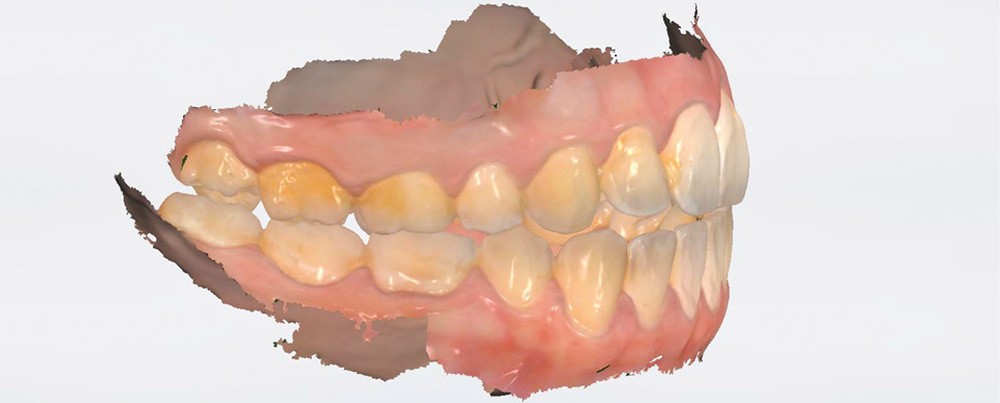

3Shape, avec Trios 4 (fig. 3a), propose 2 types de détection :

– par fluorescence (sans changement d’embout) ;

– par transillumination (avec embout dédié (fig. 3b)).